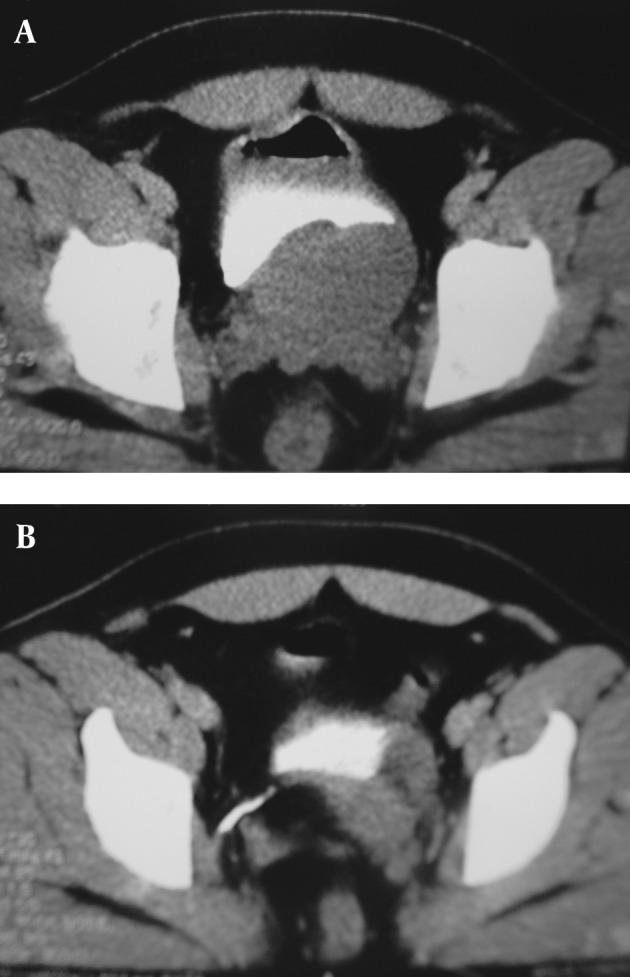

Adult ureteroceles are generally known as simple ureteroceles with minimal obstructive effects 1 that can usually be managed endoscopically. Such pathology presented with acute abdominal pain and fever in a 32-year-old man with left renal agenesia, a cranial blind left ureter and left obstructed ureterocele. The retained secretions were suppurative.

https://cdn.ncbi.nlm.nih.gov/pmc/blobs/4887/3618906/72516c176d24/iranjradiol-10-45-g001.jpg